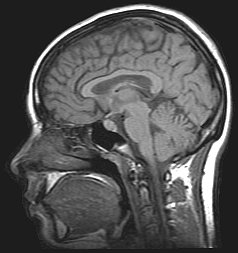

For the diagnosis, brain scans (such as MRI) should be done to rule out other potential causes.

Neuroimaging, usually with computed tomography (CT/CAT) or magnetic resonance imaging (MRI), is used to exclude any mass lesions. In IIH these scans typically appear to be normal, although small or slit-like ventricles, dilatation and buckling[18] of the optic nerve sheaths and "empty sella sign" (flattening of the pituitary gland due to increased pressure) and enlargement of Meckel's caves may be seen.